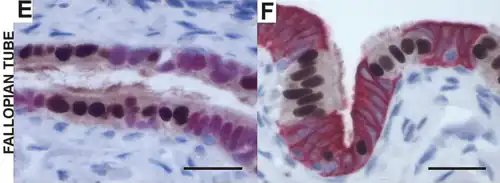

Histología

La pared de las trompas en su cara interna (luminal) es compleja. La mucosa está dispuesta sobre pliegues longitudinales denominados "plicas".

La estructura histológica varía en los diferentes segmentos, lo que permite una funcionalidad adaptada en cada uno. Se observan tres capas tisulares diferentes mucosa (endosalpinge), muscular (miosalpinge) y serosa, sus proporciones varían en los distintos segmentos.[12][13]

Internamente, cada oviducto está cubierto de una mucosa con pliegues ("plicas"), con un epitelio cilíndrico pseudoestratificado con células ciliadas, células caliciformes y células no ciliadas intercalares (o peg). Las células epiteliales descansan sobre una lámina basal y una lámina propia conjuntiva laxa subyacente.

La capa media contiene músculo liso, donde se puede distinguir una capa circular interna y otra longitudinal externa.

La capa más externa consiste en la serosa de epitelio simple plano, con tejido conectivo subyacente donde se pueden observar grandes vasos sanguíneos y nervios.

Los cilios, ayudan a movilizar al ovocito y a su encuentro con los espermatozoides, o al cigoto para su implantación en el endometrio.